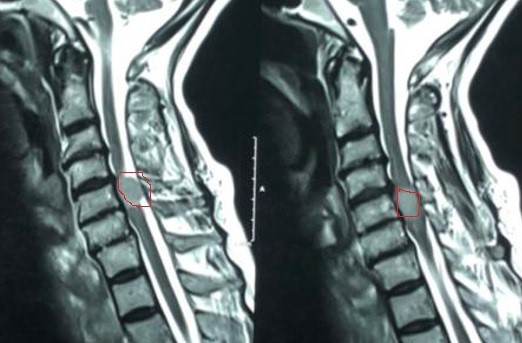

ورم سحائي بالنخاع الشوكي العنقي

meningioma of the cervical spinal cord

An image of an MRI scan of a 62-year-old female patient suffering from stiff partial quadriplegia, which led to movement impairment. And he found a meningioma pressing on the spinal cord in a way that the tumor occupied the nerve canal almost, shaded in red against the fifth cervical vertebra. And the pictures during the microscopic surgery to remove it, showing its location and size in yellow, and the recovery of the cervical nerves and cervical marrow from pressure, shown in green. The patient recovered after the successful surgery.